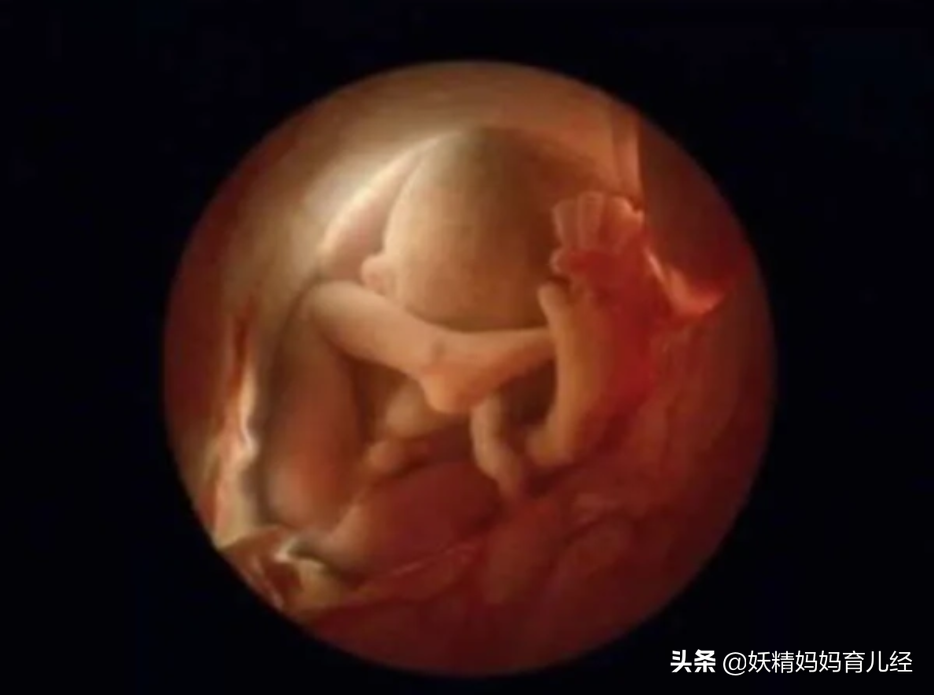

11、怀孕后的第10周,胎儿快速发育。我们已经明显的可以看出她/他已经初具人形。

12、怀孕后的16周,胎儿四肢开始活动,探索周边的世界了。这时候,很多孕妇开始感觉到胎动了。但是,宝宝的皮肤还是透明的,可以清晰看到内部的血管。